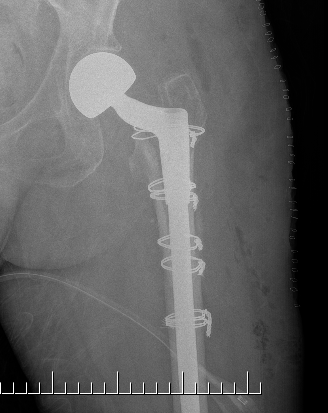

Long stem cemented revision